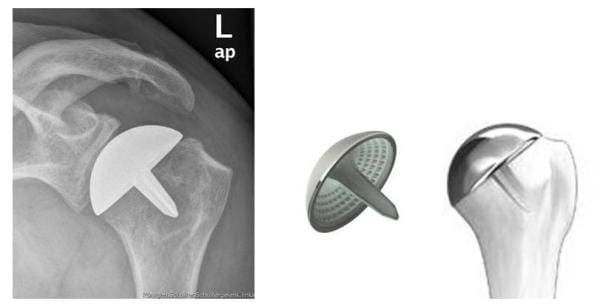

Arthrosen, die nur den Oberarmkopf betreffen, lassen sich bei guter Qualität des Knochens noch mit einer Kappenprothese behandeln. Dieses Implantat erfordert nur ein Abfräsen der beschädigten Oberfläche, welche dann durch die Kappenprothese ersetzt wird.

Röntgenbild Oberflächenersatz mit einer Kappenprothese

Röntgenbild einer Kappenprothese (Orthopädie, Klinikum Bielefeld)

Prothesenmodelle (Fa. Tornier)